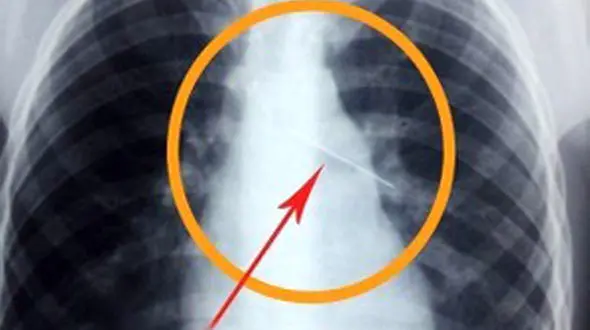

رکنا: جزئیات ماجرای دانش آموز اهوازی که سوزن را قورت داد از سوی مدیر روابط عمومی آموزش و پرورش خوزستان تشریح شد.